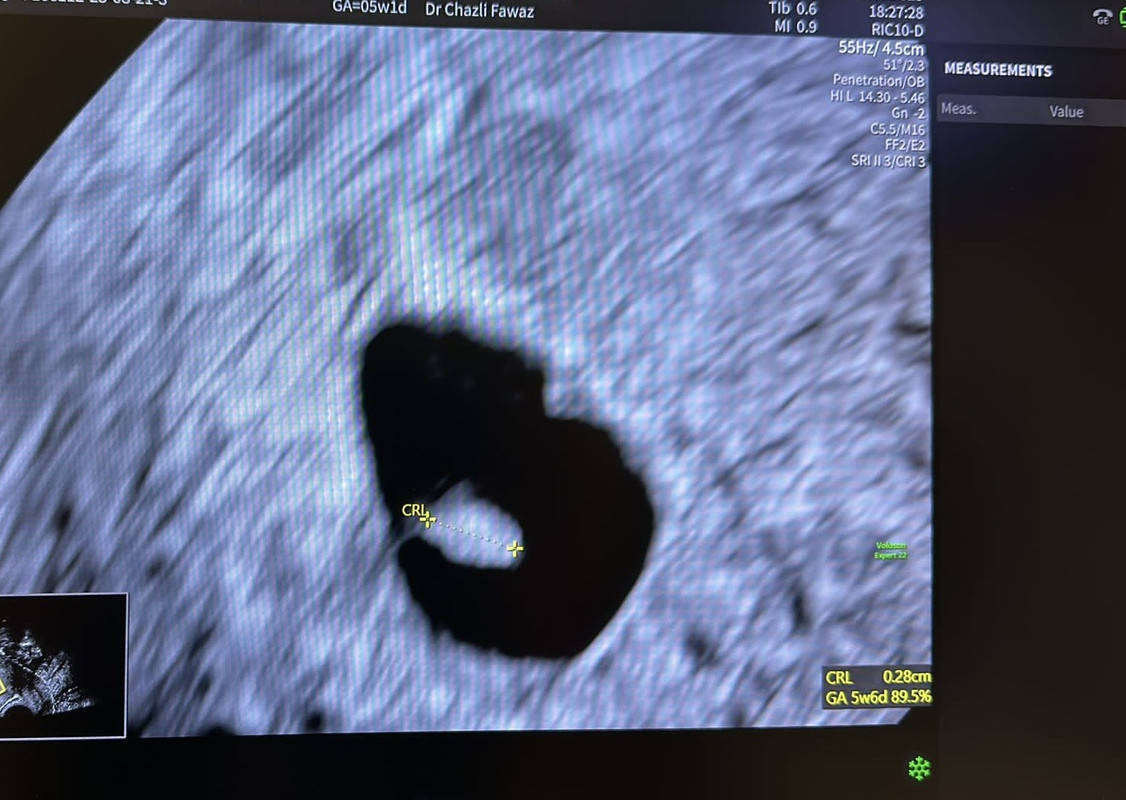

Fetelor am revenit cu vești. Am fost la medic astăzi. Conform menstruatiei aș avea 5s și 1 zii, însă ecografic aveam 5s 6zile, așa cum bănuiam, am ovulat mai devreme decât zicea aplicația. S-au văzut sacul, vezicula vitelina,chiar și embrionul micutttt. Se vedea chiar și “pâlpâitul” de la inimioară la eco, însă cu sunet nu am reușit, a zis medicul ca e prea firav acum și ca ne vedem peste 2 săptămâni. Medicul mi-a zis ca toate lucrurile sunt bune și să fiu optimistă. 🥺

https://i.postimg.cc/J003wKzF/4723329f-9625-4fe4-9c68-13ec9186b4a7.jpg

Ce frumoos! coeur

Mă bucur mult de tot pentru veștile bune și îți doresc o sarcina ușoară în continuare!